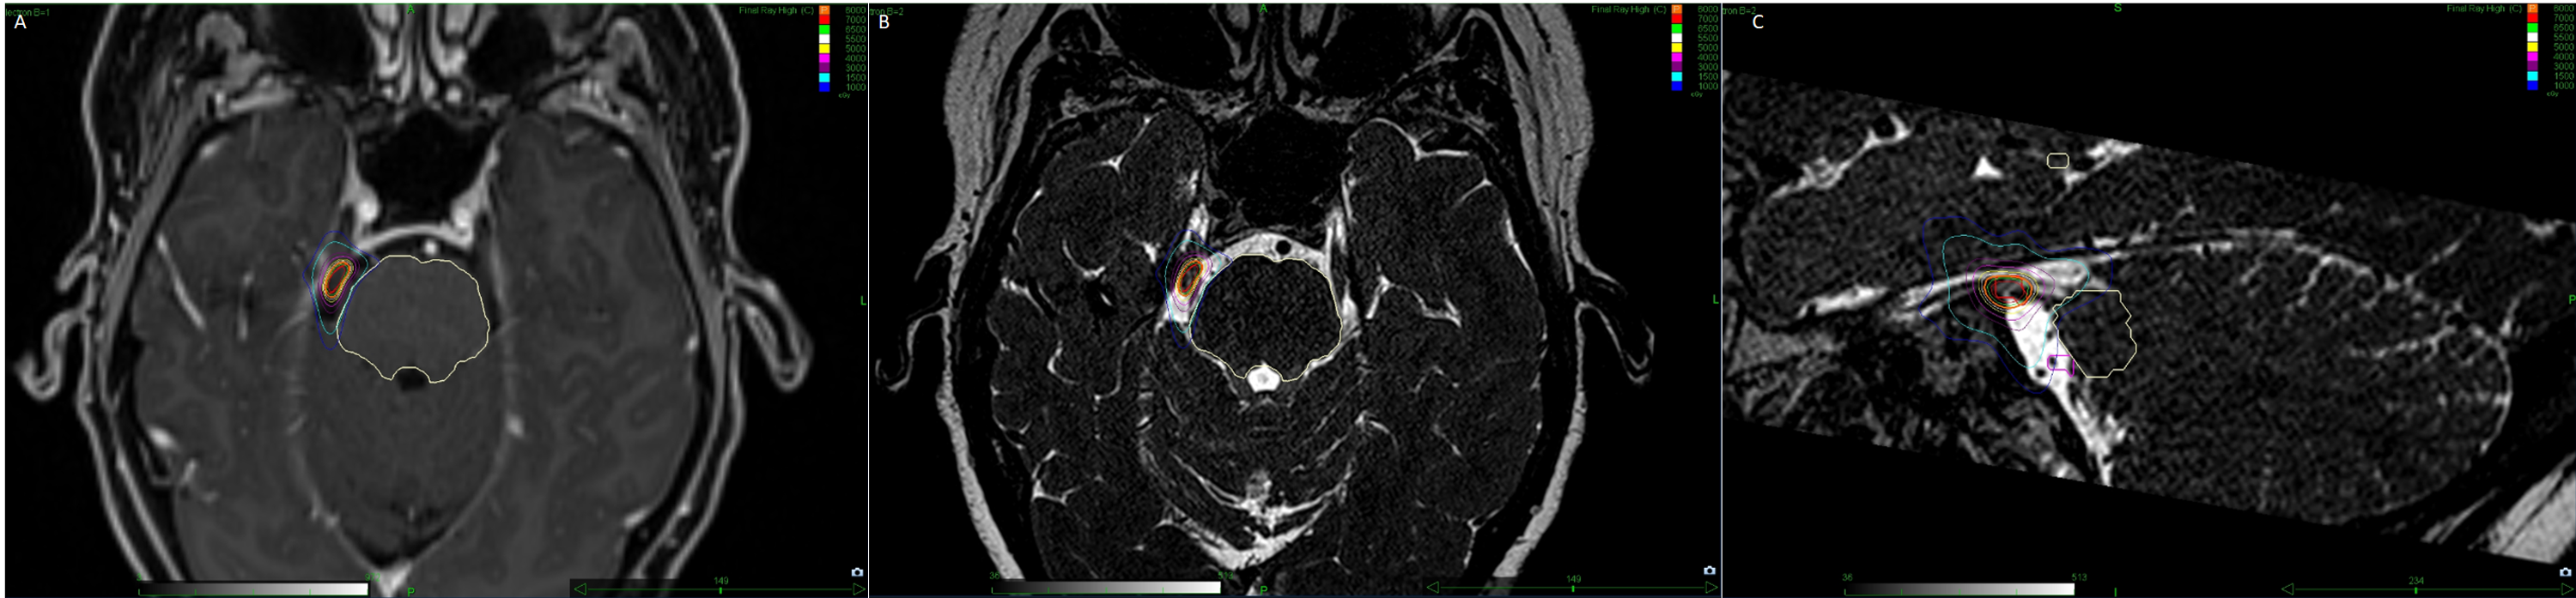

From www.semanticscholar.org

Figure 2 from The first treatment option for secondary trigeminal neuralgia open surgery versus Stereotactic Radiosurgery Trigeminal Neuralgia the purposes of this study are to assess the effectiveness of cyberknife® stereotactic radiosurgery (srs) in. The aims of this systematic review are to provide an objective summary of the published. stereotactic surgery uses focused radiation to damage nerve tissue (trigeminal nerve) to prevent or disrupt pain signals in your. the aims of this systematic review are. Stereotactic Radiosurgery Trigeminal Neuralgia.